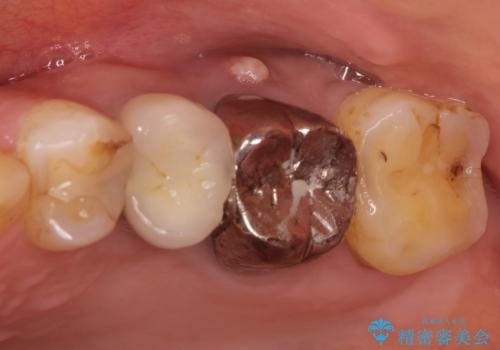

- 以前から奥歯に違和感があることを主訴に来院されました。歯肉にサイナストラクトを認めたため、再根管治療を行った後オールセラミッククラウンにて修復治療を行いました。根管治療は林先生に依頼しております。